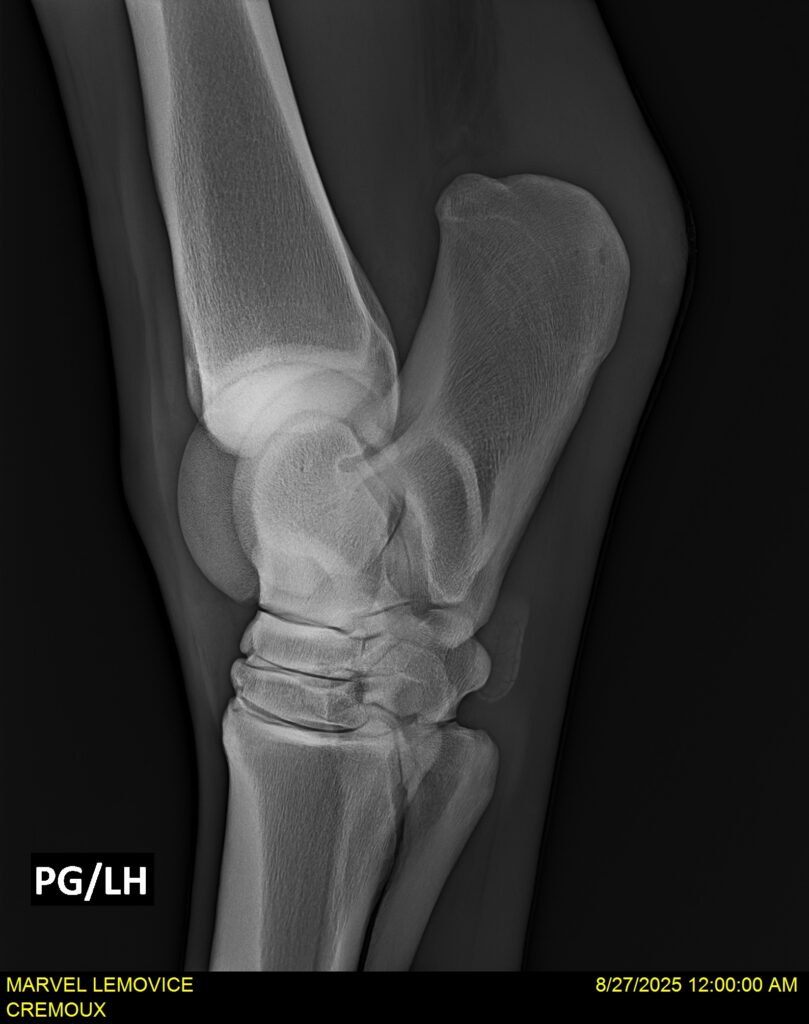

MARVEL LEMOVICE, hongre, Selle Français prend 4 ans en 2026. POPSTAR LOZONAIS x ROSIRE sur une excellente souche maternelle de l’élevage PLATIERE. Débourré aux trois allures et mise en route à l’obstacle. Super modèle avec du cadre et de la force, cheval respectueux avec des moyens. Très agréable au quotidien. Transport OK, maréchalerie OK, santé RAS, Bilan 20 clichés radios + clinique OK.

RADIOS ET CLINIQUE